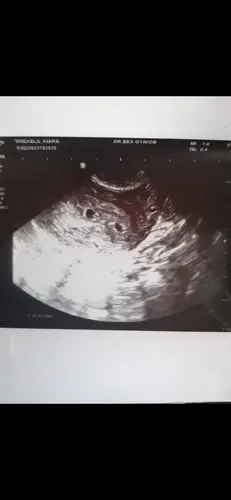

Hoi! Dit was mij echo bij 5,5 week. Dus het kan wel hoor! Maar bij mij zeid ...

Zo spannend! Ja ik was toen dus nog een week eerder dan wat jij destijds was. Ben zo benieuwd, we hebben as vrijdag weer een echo, dan 7 weken.